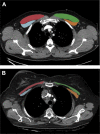

Methods: This single-center, prospective, observational cohort study included medical ICU (MICU) patients from an academic institution in the Unites States. A total of 401 patients were evaluated with pectoralis muscle area (PMA) and subcutaneous adipose tissue (SAT) determinations conducted by CT scanning at the time of ICU admission, which were later correlated with clinical outcomes accounting for potential confounders.